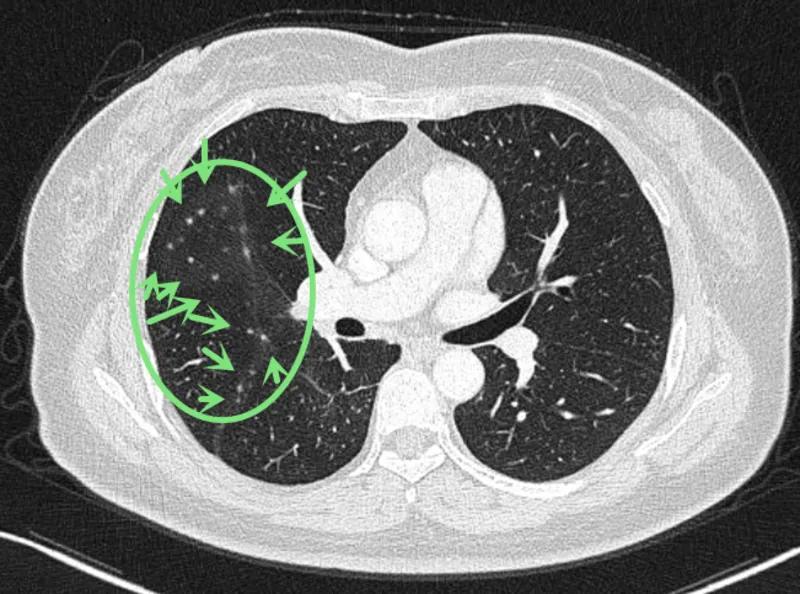

可见是右下肺达近5厘米的肿块,并上叶磨玻璃结节以及斜裂、水平裂多发微小结节。影像是如何的呢?

到底该如何考虑?下一步该如何决策?我的意见是:右下叶红色圈起来的考虑是肺癌,浸润性腺癌可能性大;右上叶磨玻璃结节粉色圈起来的考虑原位癌或不典型增生可能性大;绿色圈起来的基本上是叶裂处,从密度来看更像良性,但因为有右下叶的病灶在,也可能是种植转移,但术前较难确定。PET-CT可以考虑,但也有假阴性或假阳性。个人意见是如果没有远处其他确切转移,建议胸腔镜下探查,如果微小实性结节非转移性,则右下肺癌仍能手术的。如果真若是转移,也可取行病理依据,并送基因检测与免疫组化等检查,而单孔胸腔镜下探查下创伤小,恢复快,当然若不是转移,顺便镜下行右下叶切除并清扫淋巴结就行。